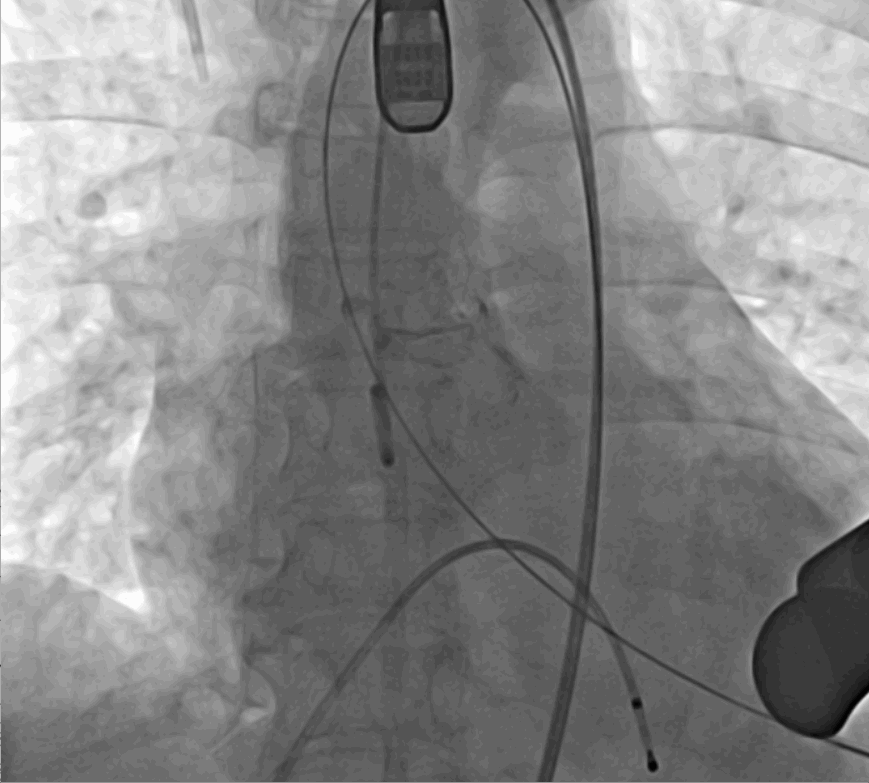

術前DSA影像圖